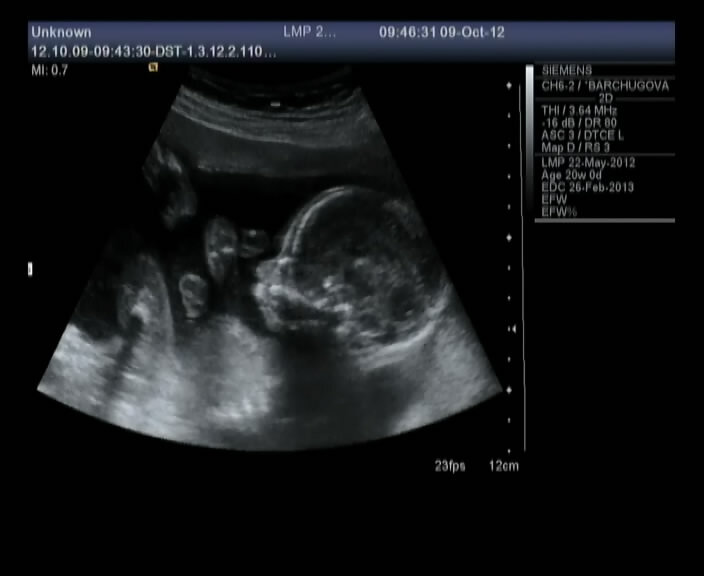

20 недель. Вот таким мы его увидели, мне кажется именно на этом сроке самое интересное УЗИ))